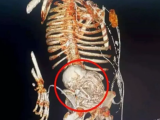

激しい腹痛を訴え、病院に担ぎ込まれた34歳の男性。食事も喉を通らないほどの痛みに苦しむ彼を診察した医師たちは、その原因を突き止めるべくX線撮影を行った。そして、現像された画像を見た瞬間、その場にいた誰もが我が目を疑った。彼の体内に写っていたのは、腫瘍でも結石でもない。なんと、食道に突き刺さった「腕時計」と、腸に詰まったおびただしい数の「ナットとボルト」だったのだ。

この衝撃的な事件が起きたのは、インドのジャイプールにあるサワイ・マン・シング病院だ。男性の体内から異物を摘出するため、緊急手術が決定。当初は内視鏡による除去が試みられたが、あまりの異物の多さに断念。腹部を小さく切開し、3時間にも及ぶ大手術の末、ついにすべての異物が取り出された。

手術室で撮影された映像には、医師たちが男性の体内から、次々と金属片を摘出する様子が生々しく記録されている。腕時計、ナット、ボルト…。まるで工具箱を丸ごと飲み込んだかのような、信じがたい光景だ。幸いにも手術は成功し、男性は順調に回復しているという。

今回のインドの男性が、なぜ腕時計やナット、ボルトを飲み込んでしまったのか。その動機は、まだ明らかにされていない。しかし、彼の腹部に写し出されたX線写真は、人間の心の闇が、時に我々の想像を絶する、不可解な行動を引き起こすという事実を物語っているのかもしれない。